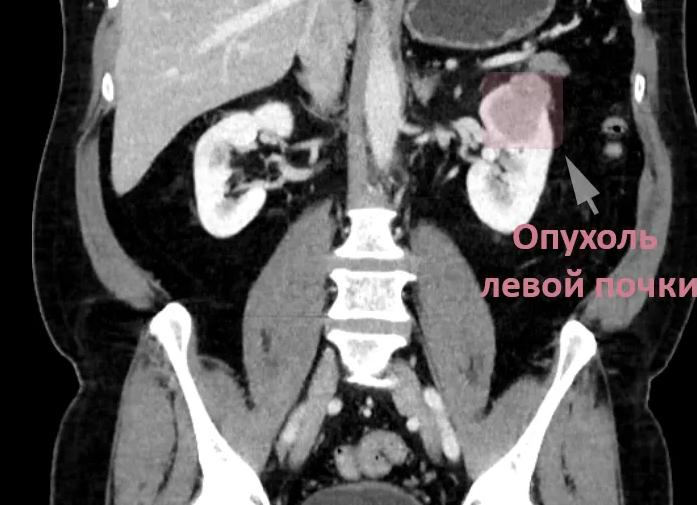

Различные образования и опухоли почки могут изменять ее размеры и форму, плотность их также отличается от плотности самого органа:

киста визуализируется при исследовании в виде гладкой тонкостенной структуры, имеющей резко очерченные границы, и обладающей меньшей плотностью, чем паренхима почки; рак неоднороден по плотности и имеет менее четкие границы; при контрастировании опухоли выглядят плотнее, чем кистозные образования, но уступают почечной паренхиме; новообразования с очагами кровоизлияний, обызвествления или некроза обладают повышенной плотностью; опухоли, происходящие из сосудистой ткани, при использовании контрастного вещества становятся более четкими; опухоли надпочечников визуализируются как структуры, которые обычно отделены от органов забрюшинного пространства.